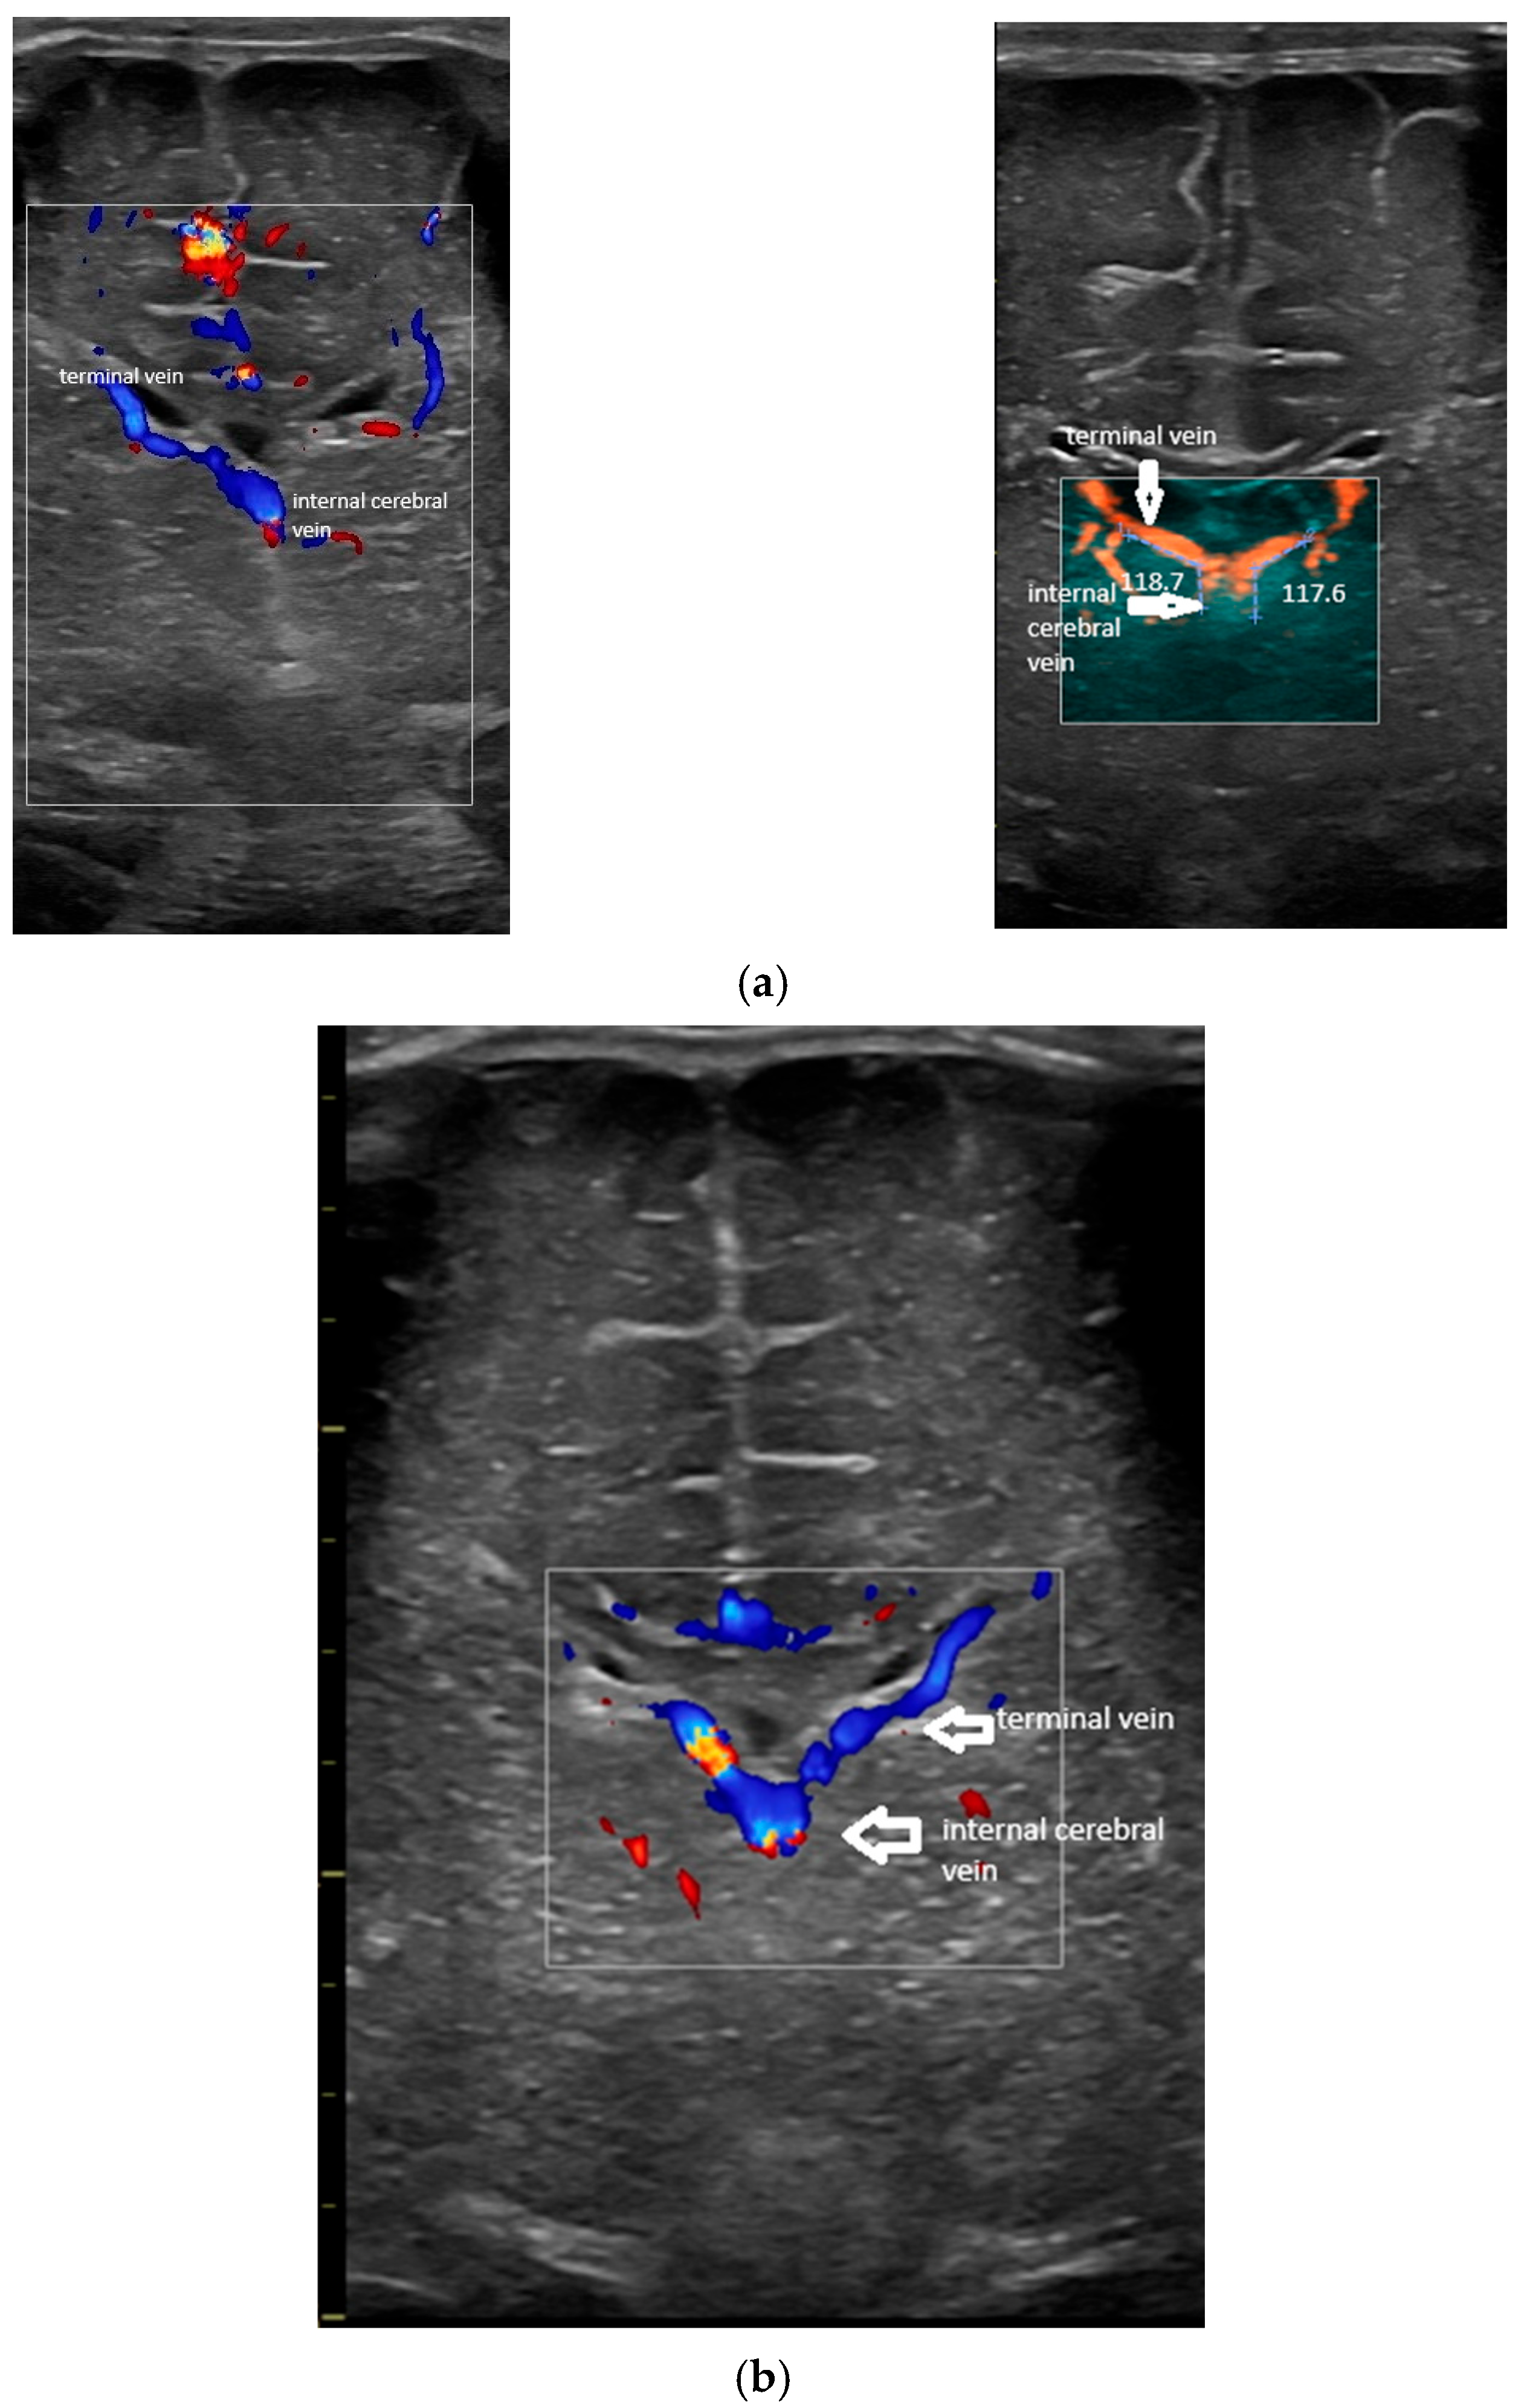

- To determine the normal values of the angles at the confluence between the terminal vein and the internal cerebral vein;

- The angles at the confluence of the terminal and internal cerebral vein on the left and right.